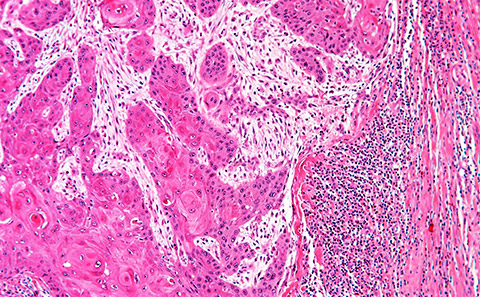

Microscope image of human cancer.

Microscope image of human cancer. Black dots on right side are lymphocytes being stopped by CAFs.

Immunotherapy works by triggering the body’s own immune system or ‘T-cells’ to recognise and attack cancer cells and has been successful in treating many types of cancer. However, for a large number of patients, the treatment is ineffective due to a protective barrier of cells called cancer assisted fibroblasts (CAFs) sitting around the tumour that our T-cells cannot penetrate.